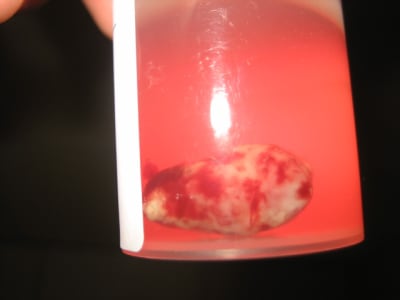

ça a pas vraiment l'aspect d'une épulis.

Tu parles de développement rapide, précises.

Pas de lésion osseuse sous-jacente?

C'est pas très sympathique ton truc:carcinome?

d'après le patient la lésion est apparue depuis 1 mois 1/2

environ.

elle saignait abondamment maintenant moins mais c'est clair que c'est pas jojo !!

la couleur violacée fait penser a un contenu hémorragique.

La surface semble etre bien différenciée.

la lesion elementaire est un nodule pédiculée..

diag differentiel à mon avis

-kyste median palatin ki sest developpé +++

-epulis vasculaire

- cancer non je pense pas.

- botryomycome ++++

- névrome de la papille

-bulle a contenu hémorrhagique

-nodule revelateur de sarcoidose ( rare++ )

Bon honnêtement j'ai lu ca le 1 er Avril, et j'ai pas vu que ca datait ou alors le coup est bien monté, mais ca ressemble bien à un abat de lapin ou de poulet pour ceux qui savent depioter ces bestioles

Perso, je balance un scan de la face antérieur de la face, car je suspecte une expulsion du paquet vasculo nerveux du trou incisif antérieur donc obligatoirement, un salle truc au dessus. Hygiène médiocre, perso ca sent pas bon, je conseille au praticien qui s'occupe de ça, de faire fermer la bouche au patient, patient allongé, que le praticien mette sa bouche sur le nez du patient et aspire très très fort, ca devrait remonter tout seul....

Evagination d'un kyste globulo-maxillaire

Diagnostique ?

Conduite à tenir : pas besoin de bilan sanguin. Exérèse au bistouri froid puis hémostase au bistouri électrique si tu en as un, sinon par simple compression çà devrait suffire + anapath.

et voilà le résultat de l'anapath :

il s'agit d'un granulome pyogénique (botryomicome)

c'est bénin et c'est très bien comme ça !!!